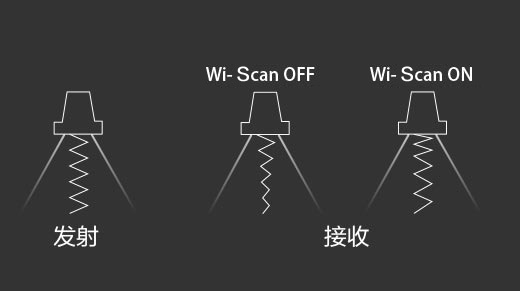

随着组织深度的变化,超声接收频率进行智能匹配跟踪,确保图像中、远场良好的穿透力以及整场一致的分辨力,从而得到均一的画质。